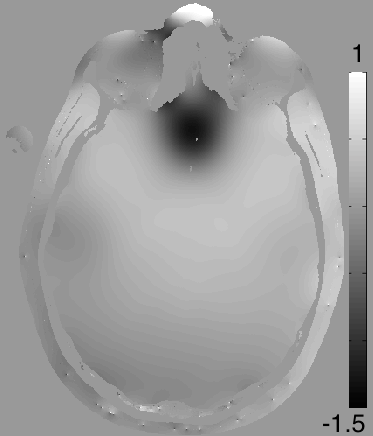

Figure 5: Background suppression of a ppm map in a healthy volunteer. (a): Magnitude of the first echo of a multi echo sequence. (b): PRF map estimation using ARMA technique.(c): Background suppressed PRF map. Blood vessels appear darker due to magnetic susceptibility effects. (d): Estimated background field map in ppm.

Figure 5 shows brain data, acquired using a 3T scanner (MR750; GE Healthcare Technologies, Waukesha, WI) from a healthy volunteer, using a 2D-MFGRE sequence with echo spacing = 3.4ms, number of echoes = 16, TE = 2.4 to 28.5 ms, TR = 2200 ms, flip = 60, FOV = 22cm, matrix = 320x256, slice thickness = 5mm, number of slices = 30. An ASSET calibration scan is performed, and sensitivity maps for each of the 32 coils in a 32-channel head coil are obtained. K-space is under-sampled by a factor of 2 by skipping every other frequency encoding line. The magnitude of the first echo is shown in panel (a). The reconstructed images are processed pixel wise by fitting a infinite impulse response (IIR) filter to each echo train. This was done using the Auto Regressive Moving Average (ARMA) [27] technique. The PRF of the dominant peak can be extracted from the coefficients of the IIR filter. The resulting PRF in ppm at each pixel is illustrated in Panel (b). Panel (c) shows the background corrected image. Blood vessels appear darker due to a negative ppm shift of oxidized blood. Brain structures in the mid brain also show significant contrast after applying our background suppression technique. Panel (d) shows the difference of (c) and (b), i.e. the suppressed background. Off resonance shifts can be seen in particular near air cavities near the sinus and the ears. This example demonstrates the potential of the method for quantitive estimation of PRF shifts due to magnetic susceptibility differences for different tissue types.